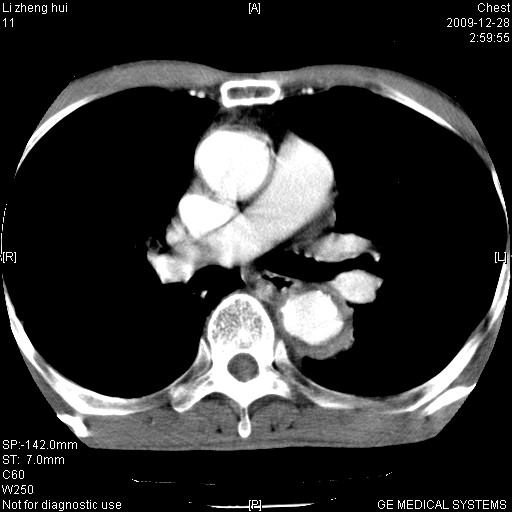

标题: CT23859:胸主动脉瘤

男  79岁 胸部痛急诊入院,晚上做的增强

考虑主动脉瘤?(增粗、钙化、壁血栓?)

动脉瘤伴附壁血栓

1)考虑胸主动脉壁间血肿或夹层动脉瘤。2)多发性肝囊肿。

1)考虑胸主动脉附壁血栓或夹层动脉瘤。2)多发性肝囊肿。